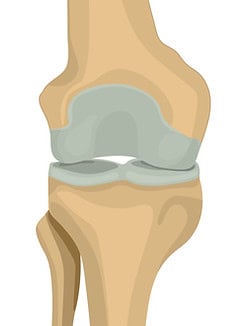

Erstes Stadium

Beginnende Arthrose

Im Gelenkbereich bilden sich kleine knöcherne Ausziehungen (Osteophyten)als Reaktion auf die beginnende Knorpelabnutzung und als Versuch des Körpers, das Gelenk zu schützen. In diesem Stadium ist der Gelenkspalt noch nicht wesentlich verengt, etwa 10 Prozent des Knorpelssind abgenutzt, und Schmerzen treten in der Regel noch nicht auf.